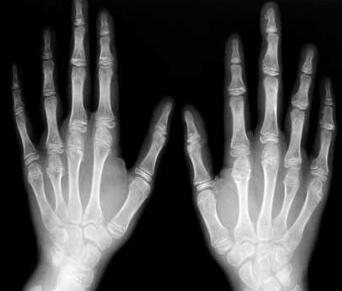

(图:王女士在入院前,手指变形)

检查:双手指间肿胀,双手关节变形,压痛明显,双手腕关节肿胀压痛,活动受限。检验:血沉90mm/h,类风湿因子116IU/ml,C-反应蛋白42.5mg/L,X线表示:双髋关节间隙模糊,关节面粗糙,指关节间隙变窄,关节变形。

(图:王女士来我院复查,X光图可清楚看到手部关节恢复健康)